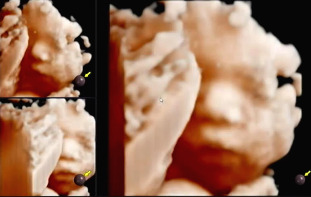

이번에는 일반 초음파뿐 아니라 입체 초음파도 예약되어 있어서 많은 기대를 하였다. 입체 초음파의 경우 일반 초음파보다 태아를 더 면밀하게 확인이 가능하고, 흑백으로 나오는 것이 아닌 주황빛을 띄는 이미지를 보여주기 때문에 기대가 되었다.

일반 복부 초음파를 보면서 의사가 태아의 성장을 확인하고 나면 입체 초음파는 따로 초음파 검사실에 있는 초음파실 선생님이 확인한다. 입체 초음파를 시행하는 경우 태아의 상태에 따라 소요시간이 달라진다. 아기가 자신을 잘 보여준다면 금방 끝이 나지만 손으로 얼굴을 가리는 등의 잘 보여주지 않을 경우 오래 걸리기도 하고 다음번에 다시 한번 초음파를 확인하기도 한다.

입체 초음파 또한 복부초음파처럼 침대에 누워 태아의 상태를 확인하는데 정밀검사처럼 태아의 손, 발뿐 아니라 얼굴 생김새까지 확인이 가능하다.

바른 자세로 누워 초음파를 시작했다. 손가락, 발가락뿐 아니라 양측 귀까지 입체 초음파를 통해 확인하고 태아의 얼굴 생김새를 확인했다. 일반 초음파로 확인할 때와 다르게 입체적으로 보이는 태아의 모습에 신기했다.